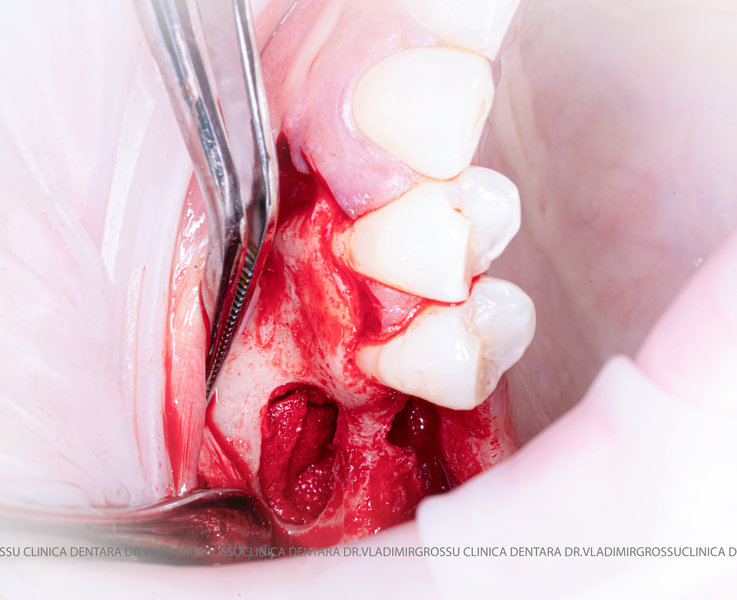

Stomatologia estetică reprezintă în prezent una dintre direcțiile principale de specializare a medicilor clinicii Dr. Grossu din Chișinău.Adiția sau augmentarea osoasă este o procedură chirurgicală prin care se refac defectele osoase rezultate în urma extracțiilor dentare, bolii parodontale sau traumelor dento-alveolare.

După extracția dentară, în intervalul de 6-12 luni, osul alveolar suferă un proces natural de remodelare, ceea ce conduce la scăderea volumului osos prin rezorbție. De aceea, inserția implantului dentar este ideală imediat după extracție sau, cel târziu, în primele 3-4 luni după aceasta.Scopul procedurilor de adiție osoasă este refacerea fundației osoase necesare pentru stabilizarea corectă a implantului dentar. Pentru ca un implant să reziste în timp la forțele masticatorii, este nevoie de o bază osoasă solidă și sănătoasă.

Un element esențial în procedura de aditie osoasă este utilizarea membranelor biologice, care izolează materialul osos de țesuturile moi (gingie) pe durata procesului de vindecare. Cele mai recomandate sunt membranele resorbabile din colagen sau pericard.

Aditia gingivală este o procedură chirurgicală ce corectează diverse probleme estetice și funcționale, cum ar fi recesiunea gingivală. În implantologia modernă, aditia de țesut moale este utilizată aproape în fiecare intervenție de inserție a implantului dentar pentru a asigura un aspect estetic natural și o bună integrare a implantului în cavitatea bucală.